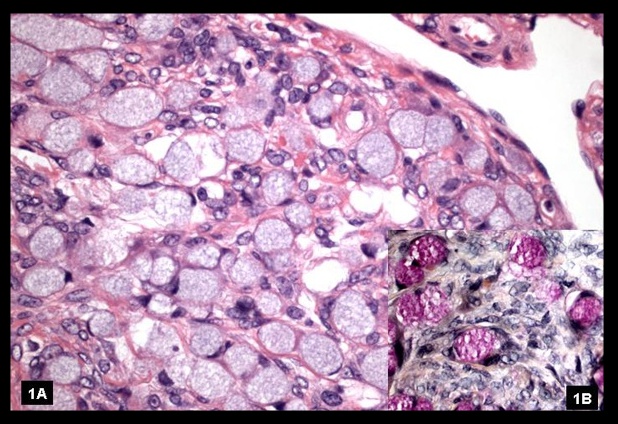

_Histology reveal cells with scanty cytoplasm and angulated, coffee-bean, grooved nuclei. The classic features are Call-Exner bodies., which are granulosa cells arranged in small follicles filled with eosinophilic secretions in the center.

Granulosa cell tumor: showing diffuse proliferation of small round cells.

Call-Exner Bodies seen in granulosa cell tumor